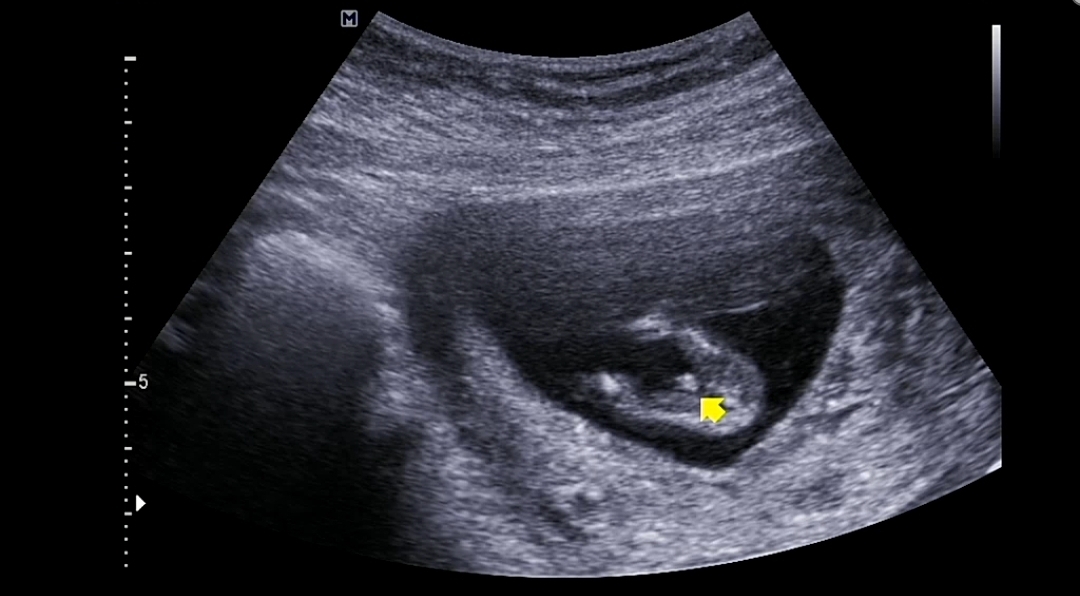

12주차 아들인가봐요 ㅎㅎ

12주차 기형아검사하고 담당 의사쌤보러갔는데 배초음파 보자마자 옷색깔알려드려요? 하시더니 마지막에 얘는 너무 아들인것같다고 ㅋㅋㅋ 신랑은 아들 저는 딸낳고 싶었는데요 ㅜㅜㅋㅋㅋㅋ